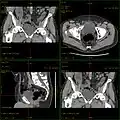

Die Übersichtsaufnahme, Topo, Scanogramm oder auch Scout-View genannt, dient lediglich der Untersuchungsplanung.

Vor jeder Aufnahme wird grundsätzlich eine Übersichtsaufnahme aufgenommen. Hierbei steht die Röntgenröhre still. Der Patient wird mit Hilfe des verfahrbaren Tisches am Fächerstrahl der Röhre vorbeigefahren. Im Ergebnis erhält man ein Bild, das einer klassischen Röntgenaufnahme sehr ähnlich sieht. Dieses Bild dient jedoch nur der Planung anschließender Aufnahmen.[1]